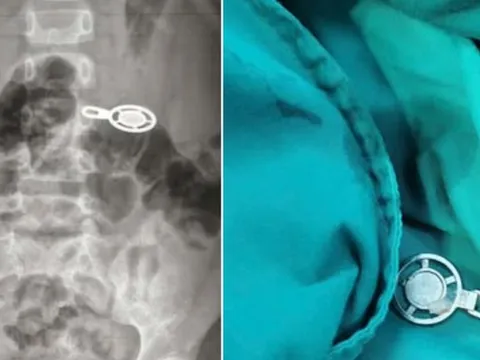

Người đàn ông 50 tuổi đau hạ vị kéo dài, bác sĩ sốc khi gắp ra thứ "đáng sợ" bằng quả trứng ngỗng

Người bệnh nhập viện trong tình trạng tiểu buốt, tiểu khó kéo dài do sỏi phát triển lớn trong bàng quang. Bác sĩ lập tức lấy ra viên sỏi kích thước tới 60x40 mm, lớn gần bằng quả trứng ngỗng.